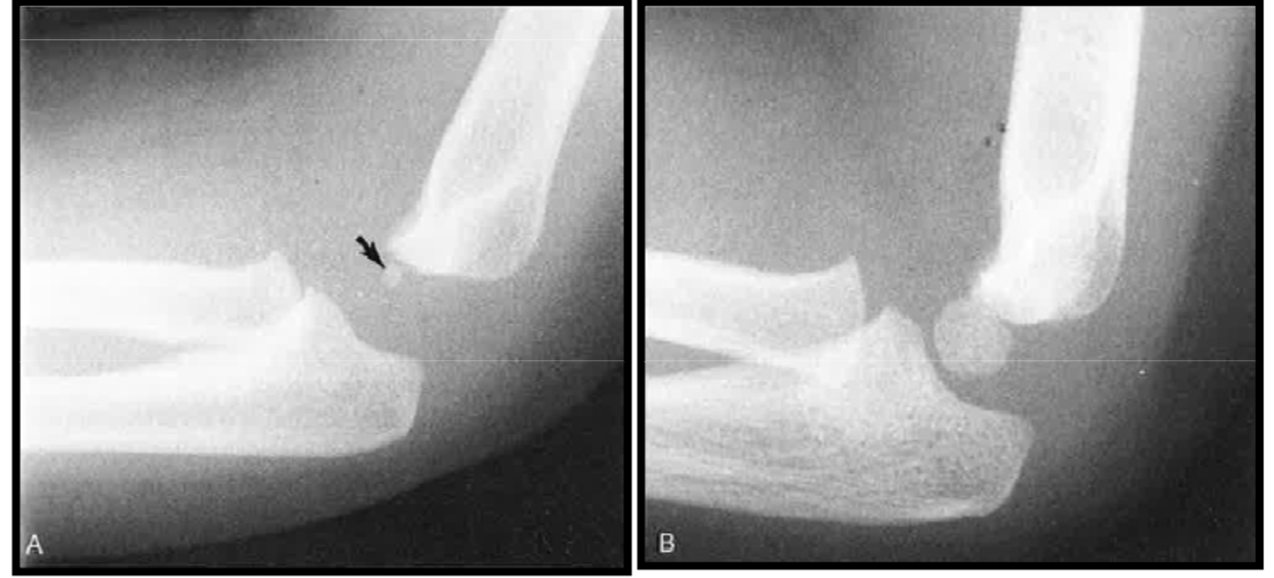

Maturation osseuse – Vues de profil

varaition anat normal

variation normal